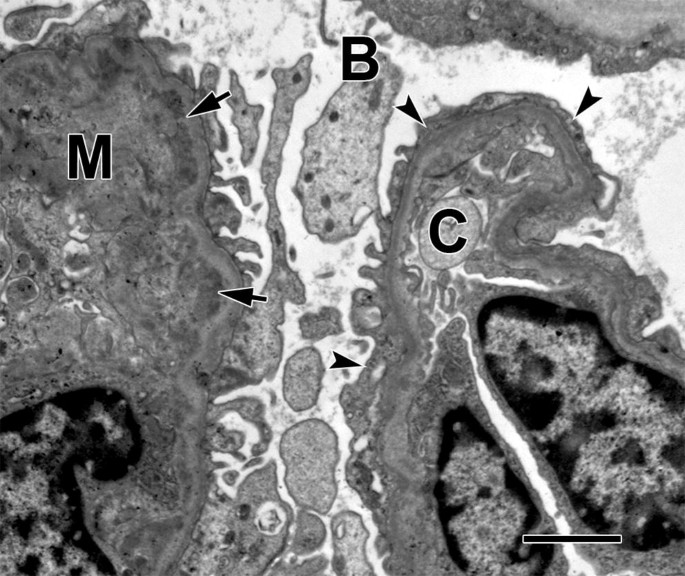

A 12-year-old male presents to the emergency department following several days of facial edema. A urinalysis confirms proteinuria and hematuria. Once admitted, a kidney biopsy is viewed under an electron microscope to confirm the diagnosis of minimal change disease. In the following electron micrograph, what process occurs in the structure marked with an arrow?